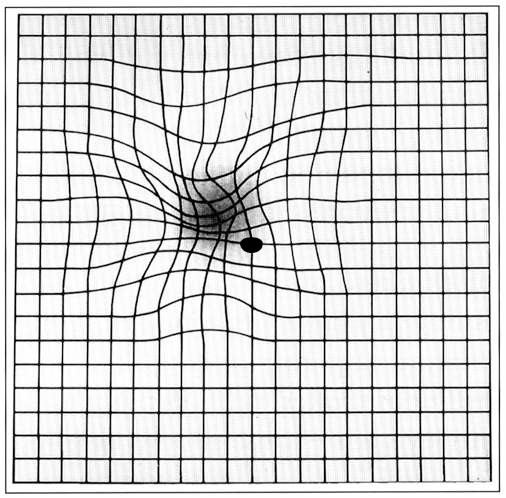

La grille d'Amsler : auto-dépistage à domicile

La grille d'Amsler est un test simple permettant de détecter précocement les métamorphopsies (déformations) et les scotomes (zones aveugles) typiques de la DMLA.

Grille d'Amsler normale et avec déformations typiques de la DMLA Test de la grille d'Amsler Grille normale Toutes les lignes sont droites et régulières Grille pathologique (DMLA) Lignes ondulées + scotome central = ALERTE Mode d'emploi 1. Portez vos lunettes de lecture 2. Placez la grille à 30 cm 3. Cachez un œil avec la main 4. Fixez le point central 5. Vérifiez que toutes les lignes sont droites et nettes 6. Répétez avec l'autre œil Lignes déformées ou zone floue ? Consultez sous 48 heures RECOMMANDATION : TEST HEBDOMADAIRE Les patients atteints de MLA ou de DMLA sèche doivent tester leur vision chaque semaine avec la grille d'Amsler pour détecter rapidement une conversion en forme humide.

Grille d'Amsler déformée telle que perçue par un patient atteint de DMLA

Grille d'Amsler déformée telle que perçue par un patient atteint de DMLA — Crédit : domaine public